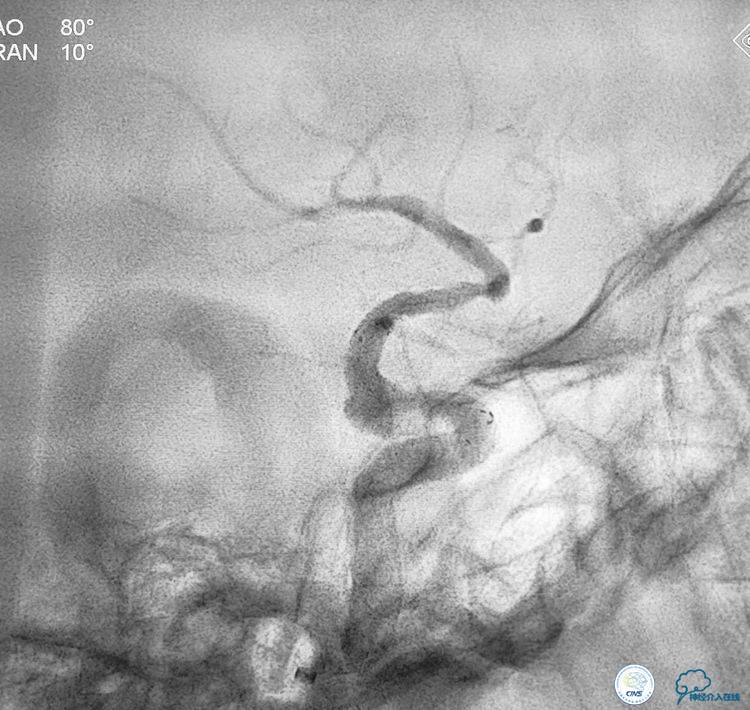

▼选择3×9mm Getway球囊进行扩张。

▼扩张后狭窄明显改善。

▼释放4.5x20 Neuroform支架。